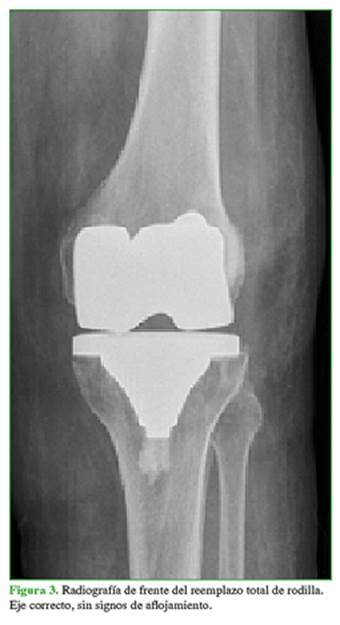

En las radiografías de frente, se visualizó un implante en posición y alineación correctas, sin signos de demarcación. En las imágenes de perfil, se pudo comprobar el recurvatum de aproximadamente 20° (Figuras 3 y 4).

La paciente tenía una rodilla con buena función clínica, caminaba sin asistencia y sin limitación desde el tercer mes posterior a la cirugía y, en las radiografías de control, se observó un eje correcto sin demarcación de la prótesis.